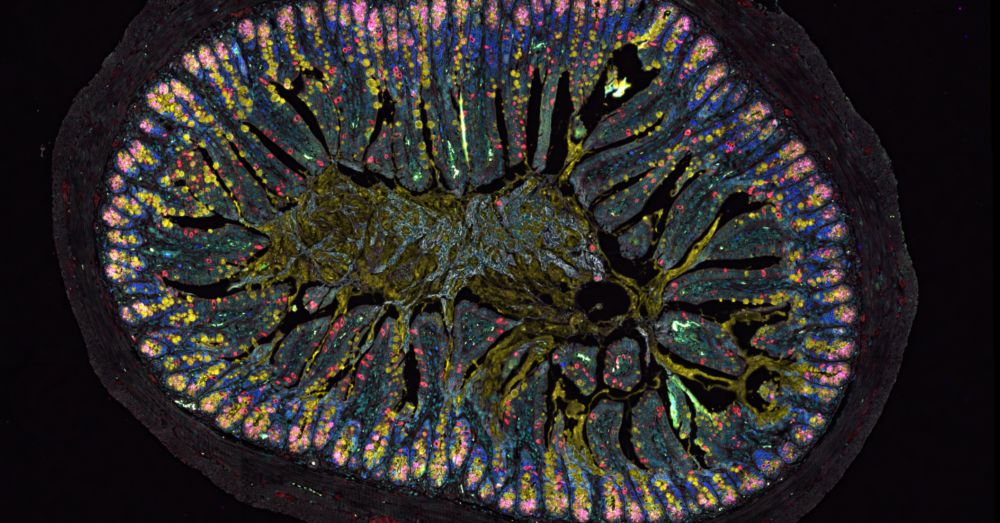

The intestinal nervous system helps maintain the stability of the intestinal barrier. 🔬🦠

Disruption of this protection, may lead to allergies, as shown in a recent study by #unibern, @inselgruppe.bsky.social & Charité Berlin 👇

Why the "gut brain" plays a central role for allergies

An international research team led by scientists from Bern and Charité – Universitätsmedizin Berlin has identified a previously unknown function of the intestinal nervous system. The study reveals tha...

Das Darmnervensystem reguliert die Zusammensetzung & Stabilität der Darmbarriere. Ist dieser Schutzmechanismus gestört, entsteht eine Neigung zu Allergien.🔬🦠

Dies zeigt eine neue Studie der #unibern, @inselgruppe.bsky.social & Charité Berlin 👇

Weshalb das «Bauchhirn» eine zentrale Rolle bei Allergien spielt

Eine internationale Studie unter Leitung von Berner Forschenden und der Charité – Universitätsmedizin Berlin hat eine bislang unbekannte Funktion des Darmnervensystems aufgedeckt. Wie das Team nun zei...